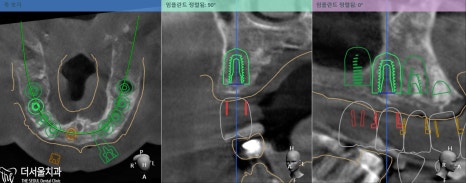

픽스처를 심기 전

수정구치과는 디지털 네비게이션을 이용하여,

각 위치에 맞는 임플란트 식립 계획을

모의 수술을 통해 꼼꼼하게 점검하고 세워봅니다.

이를 토대로 제작된 가이드를 이용해

픽스처를 빠르게 심을 수 있고,

최소 절개로 통증이 덜하며

빠른 회복이 가능합니다. ^^

다만, 여기서 알 수 있었던 사실은

16, 25, 26번의 잇몸뼈는 픽스처를 심기에

한참 모자란 상태였습니다.

그럼 보강해줘야 되겠죠?